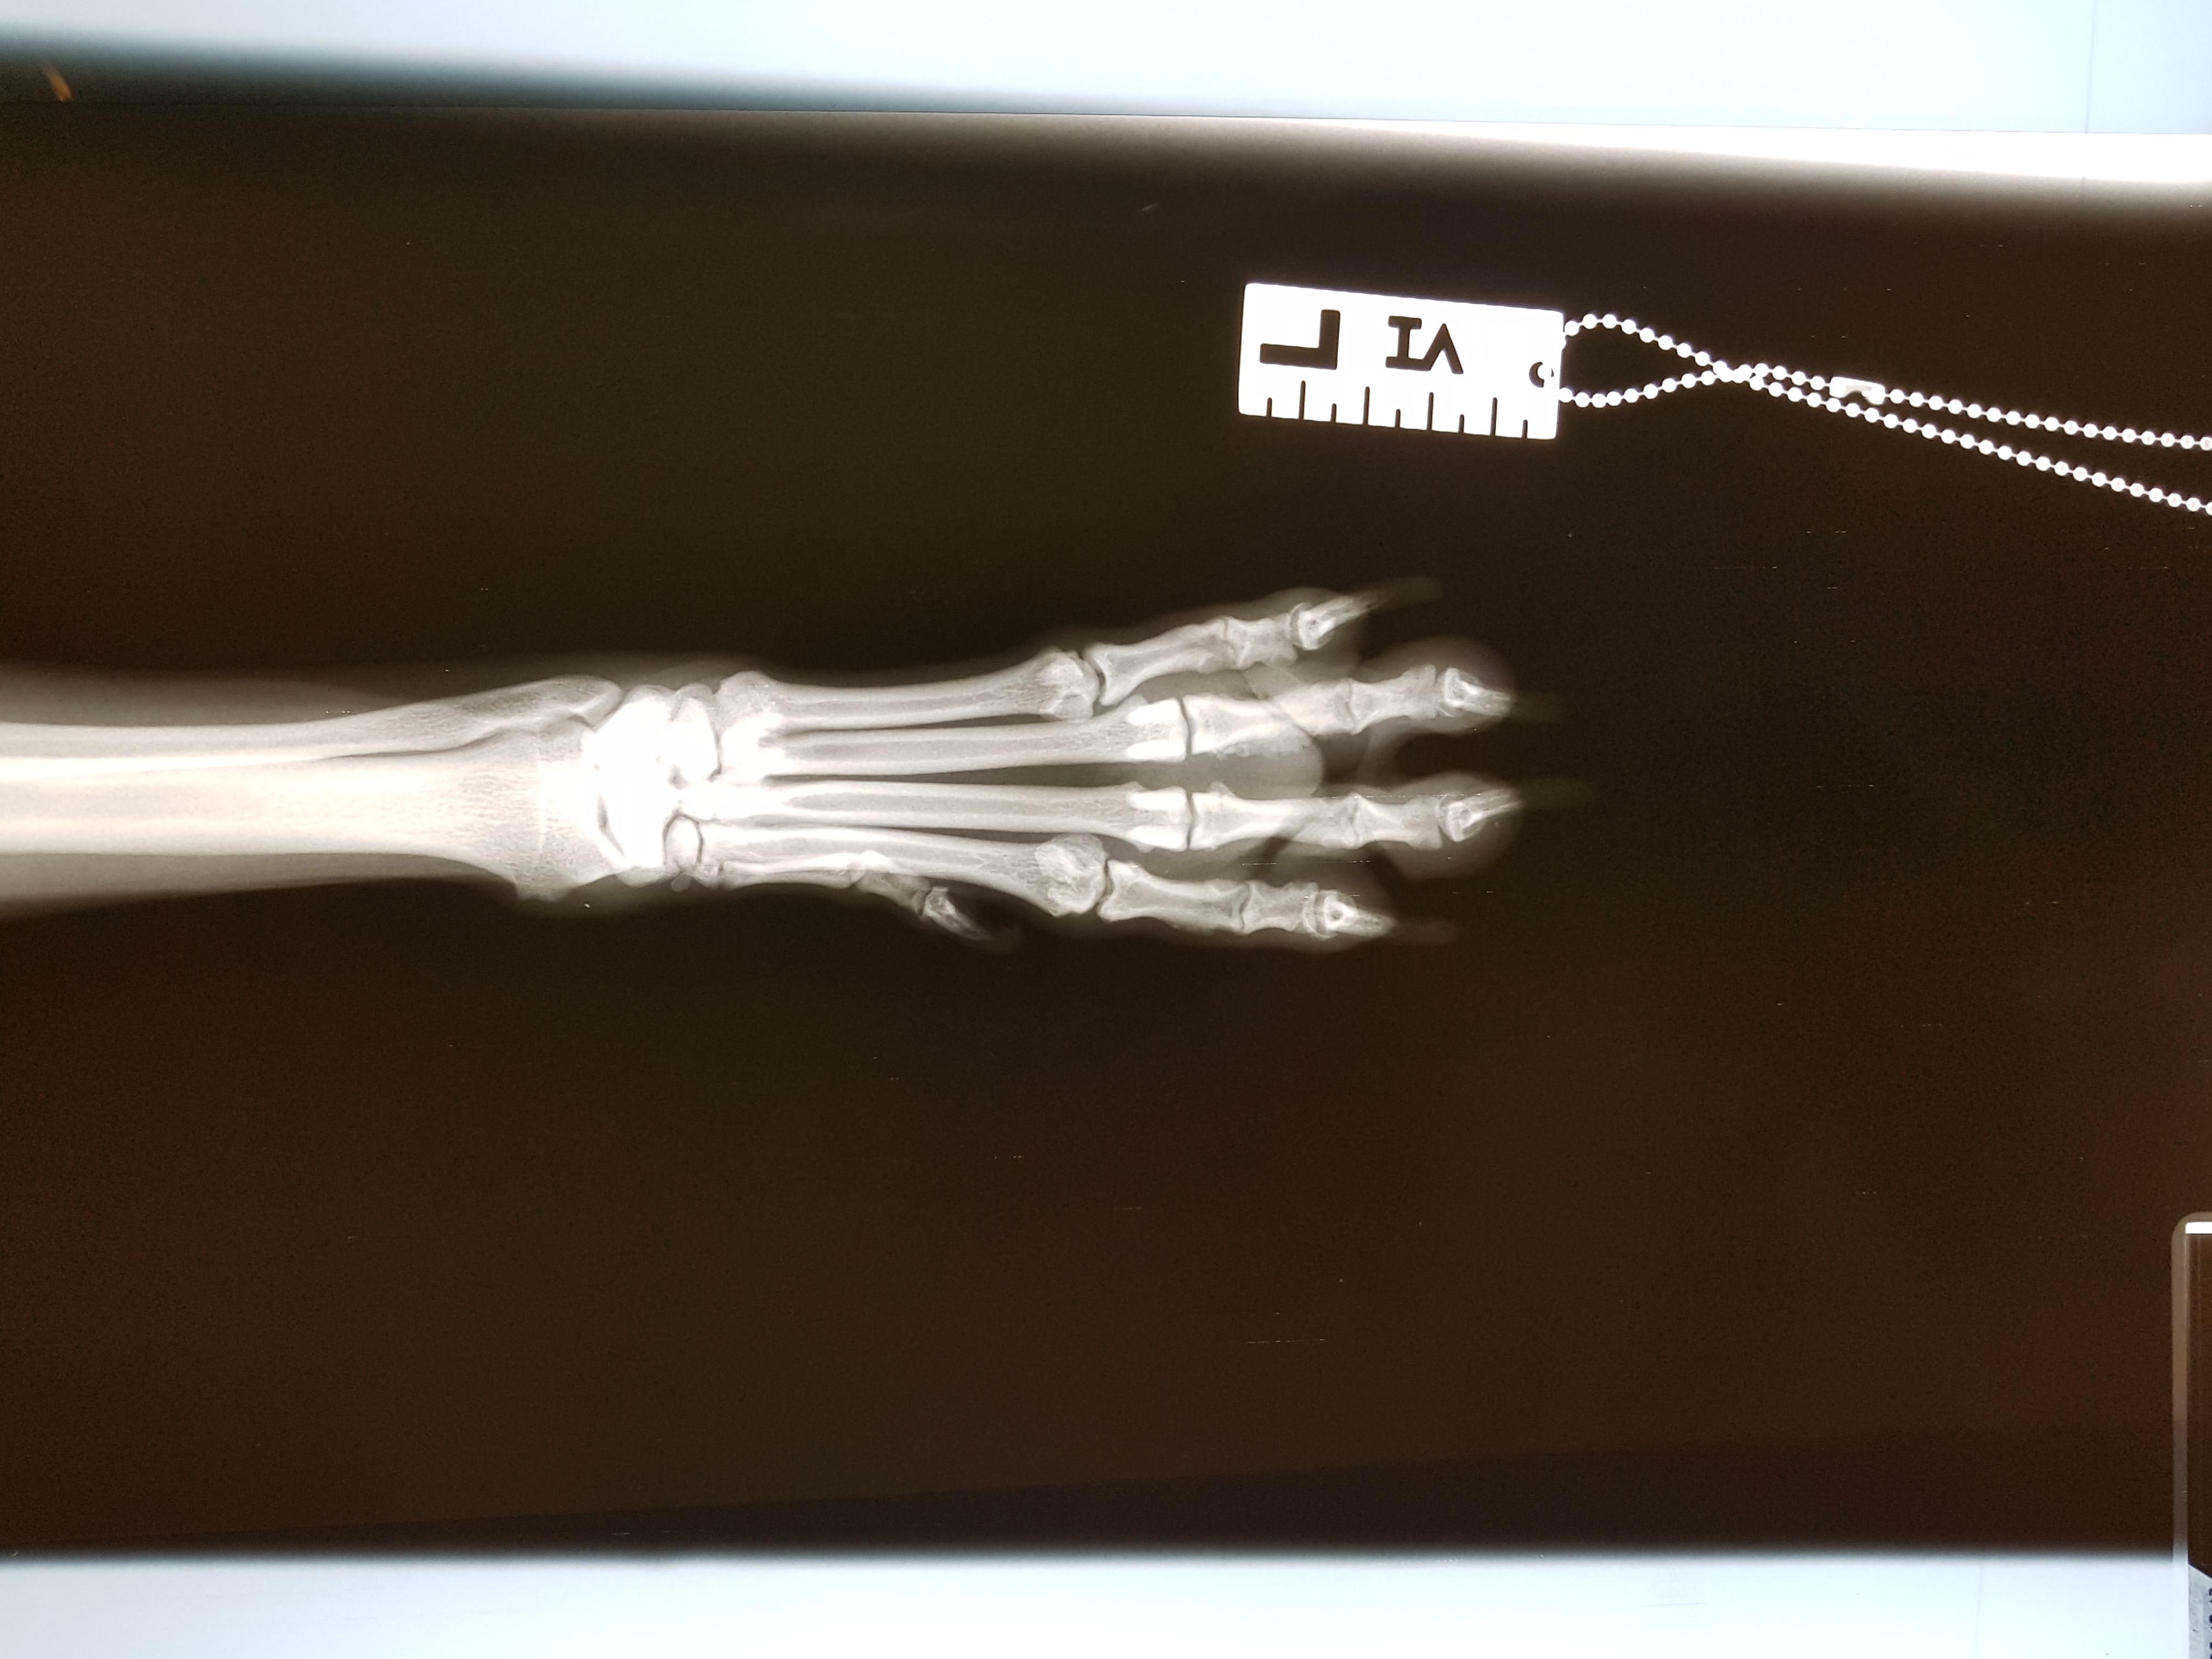

Hello. I have a 6year old female boxer lab wippet mix. She started limping while being on sea side in august. First I thought she hit her paw in a rock under the water while jumping around. Now is october and she is still limping on and off. If we go for a longer hike then she limps. Otherwise she is ok. I took her to the vet and we did some xrays. There is a mass on 3 of her toes. We are concern it's tumor. I also talked to 2 ortho vets and they both said it's exostosis. Lungs xray is ok.thanks

Hi and thanks for using Petco Pet Education Center, formerly Petcoach! Sorry to hear that Brooklyn is having intermittent lameness problems. Bone tumors, when present are usually solitary lesions involving one area of bone. So since this is in multiple places, I would highly discount any neoplastic problem. This may just be incidental findings. I would be more interested in what the hips and knee joint looks like on that leg. One very common injury that dogs encounter is an injury to the anterior or cranial cruciate ligament, much like athletes suffer. Whenever I hear intermittent lameness or non-weight bearing on a rear leg, this is the most common injury to investigate. A complete tear of the ligament usually leads to non-weight bearing and a partial tear usually results in intermittent lameness problems. But there are other causes of lameness which should be considered including hip or other joint problems (arthritis, degenerative joint disease), trauma, puncture wounds, fractures, soft tissue injuries to tendons/ligaments, muscle injuries, tick-transmitted diseases, etc. ACL injuries usually occur when dogs are chasing squirrels, cats, birds, etc across the yard. They are fine and then they return lame, holding up the leg or bearing partial weight. That ligament when examined microscopically is undergoing a degenerative process in almost all of the cases. The strain on the ligament eventually tears or rips it completely. That same process can occur in the other knee and that's why this is so important to diagnose properly. Some dogs tear one ACL, get it fixed and then tear the other one. There are multiple ways to fix an ACL rupture or tear and I would discuss these with your veterinarian. Some of the newer techniques are specialized procedures only certain vets perform and they require that hardware (plates, screws) be put into the area to stabilize the knee joint. One older technique is called the lateral imbrication technique and I still think it works well if an experienced surgeon does it. It is much cheaper also compared to the newer procedures. There are some braces out now also for dogs that are unable to have a surgical repair done but I don't have any experience with those. So I would advise taking Brooklyn back to your vet or another vet for a second opinion if this condition persists, worsens, or other signs develop. They can evaluate her again, gather a detailed history, and then make a diagnostic plan, and eventual treatment plan. A physical exam may include sedation/anesthesia and more x-rays to fully assess the leg. Good luck with Brooklyn.